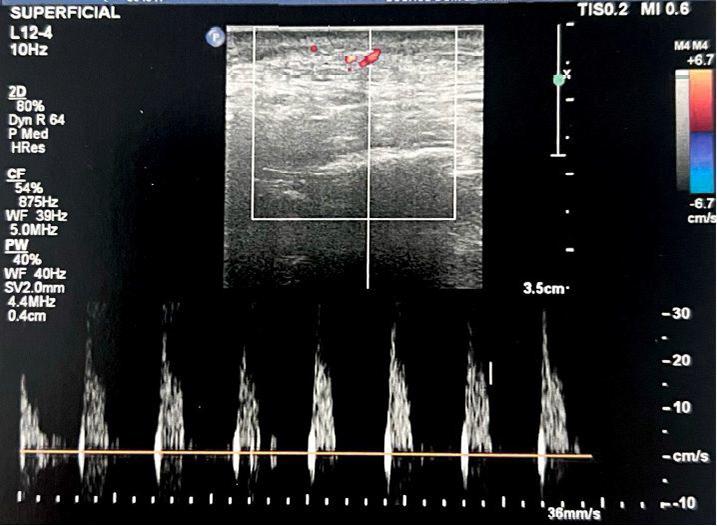

Tratamento da síndrome de Parry-Romberg e da esclerodermia linear em golpe de sabre, com aplicação do ácido

76 poli-L-láctico (PLLA): avaliação da resposta clínica e ultrassonográfica de alta resolução

Renato Roberto Liberato Rostey, Cristiane Ferreira Rallo de Almeida, Danilo Olavarria D’Aquino, Caio Leal Carvalho